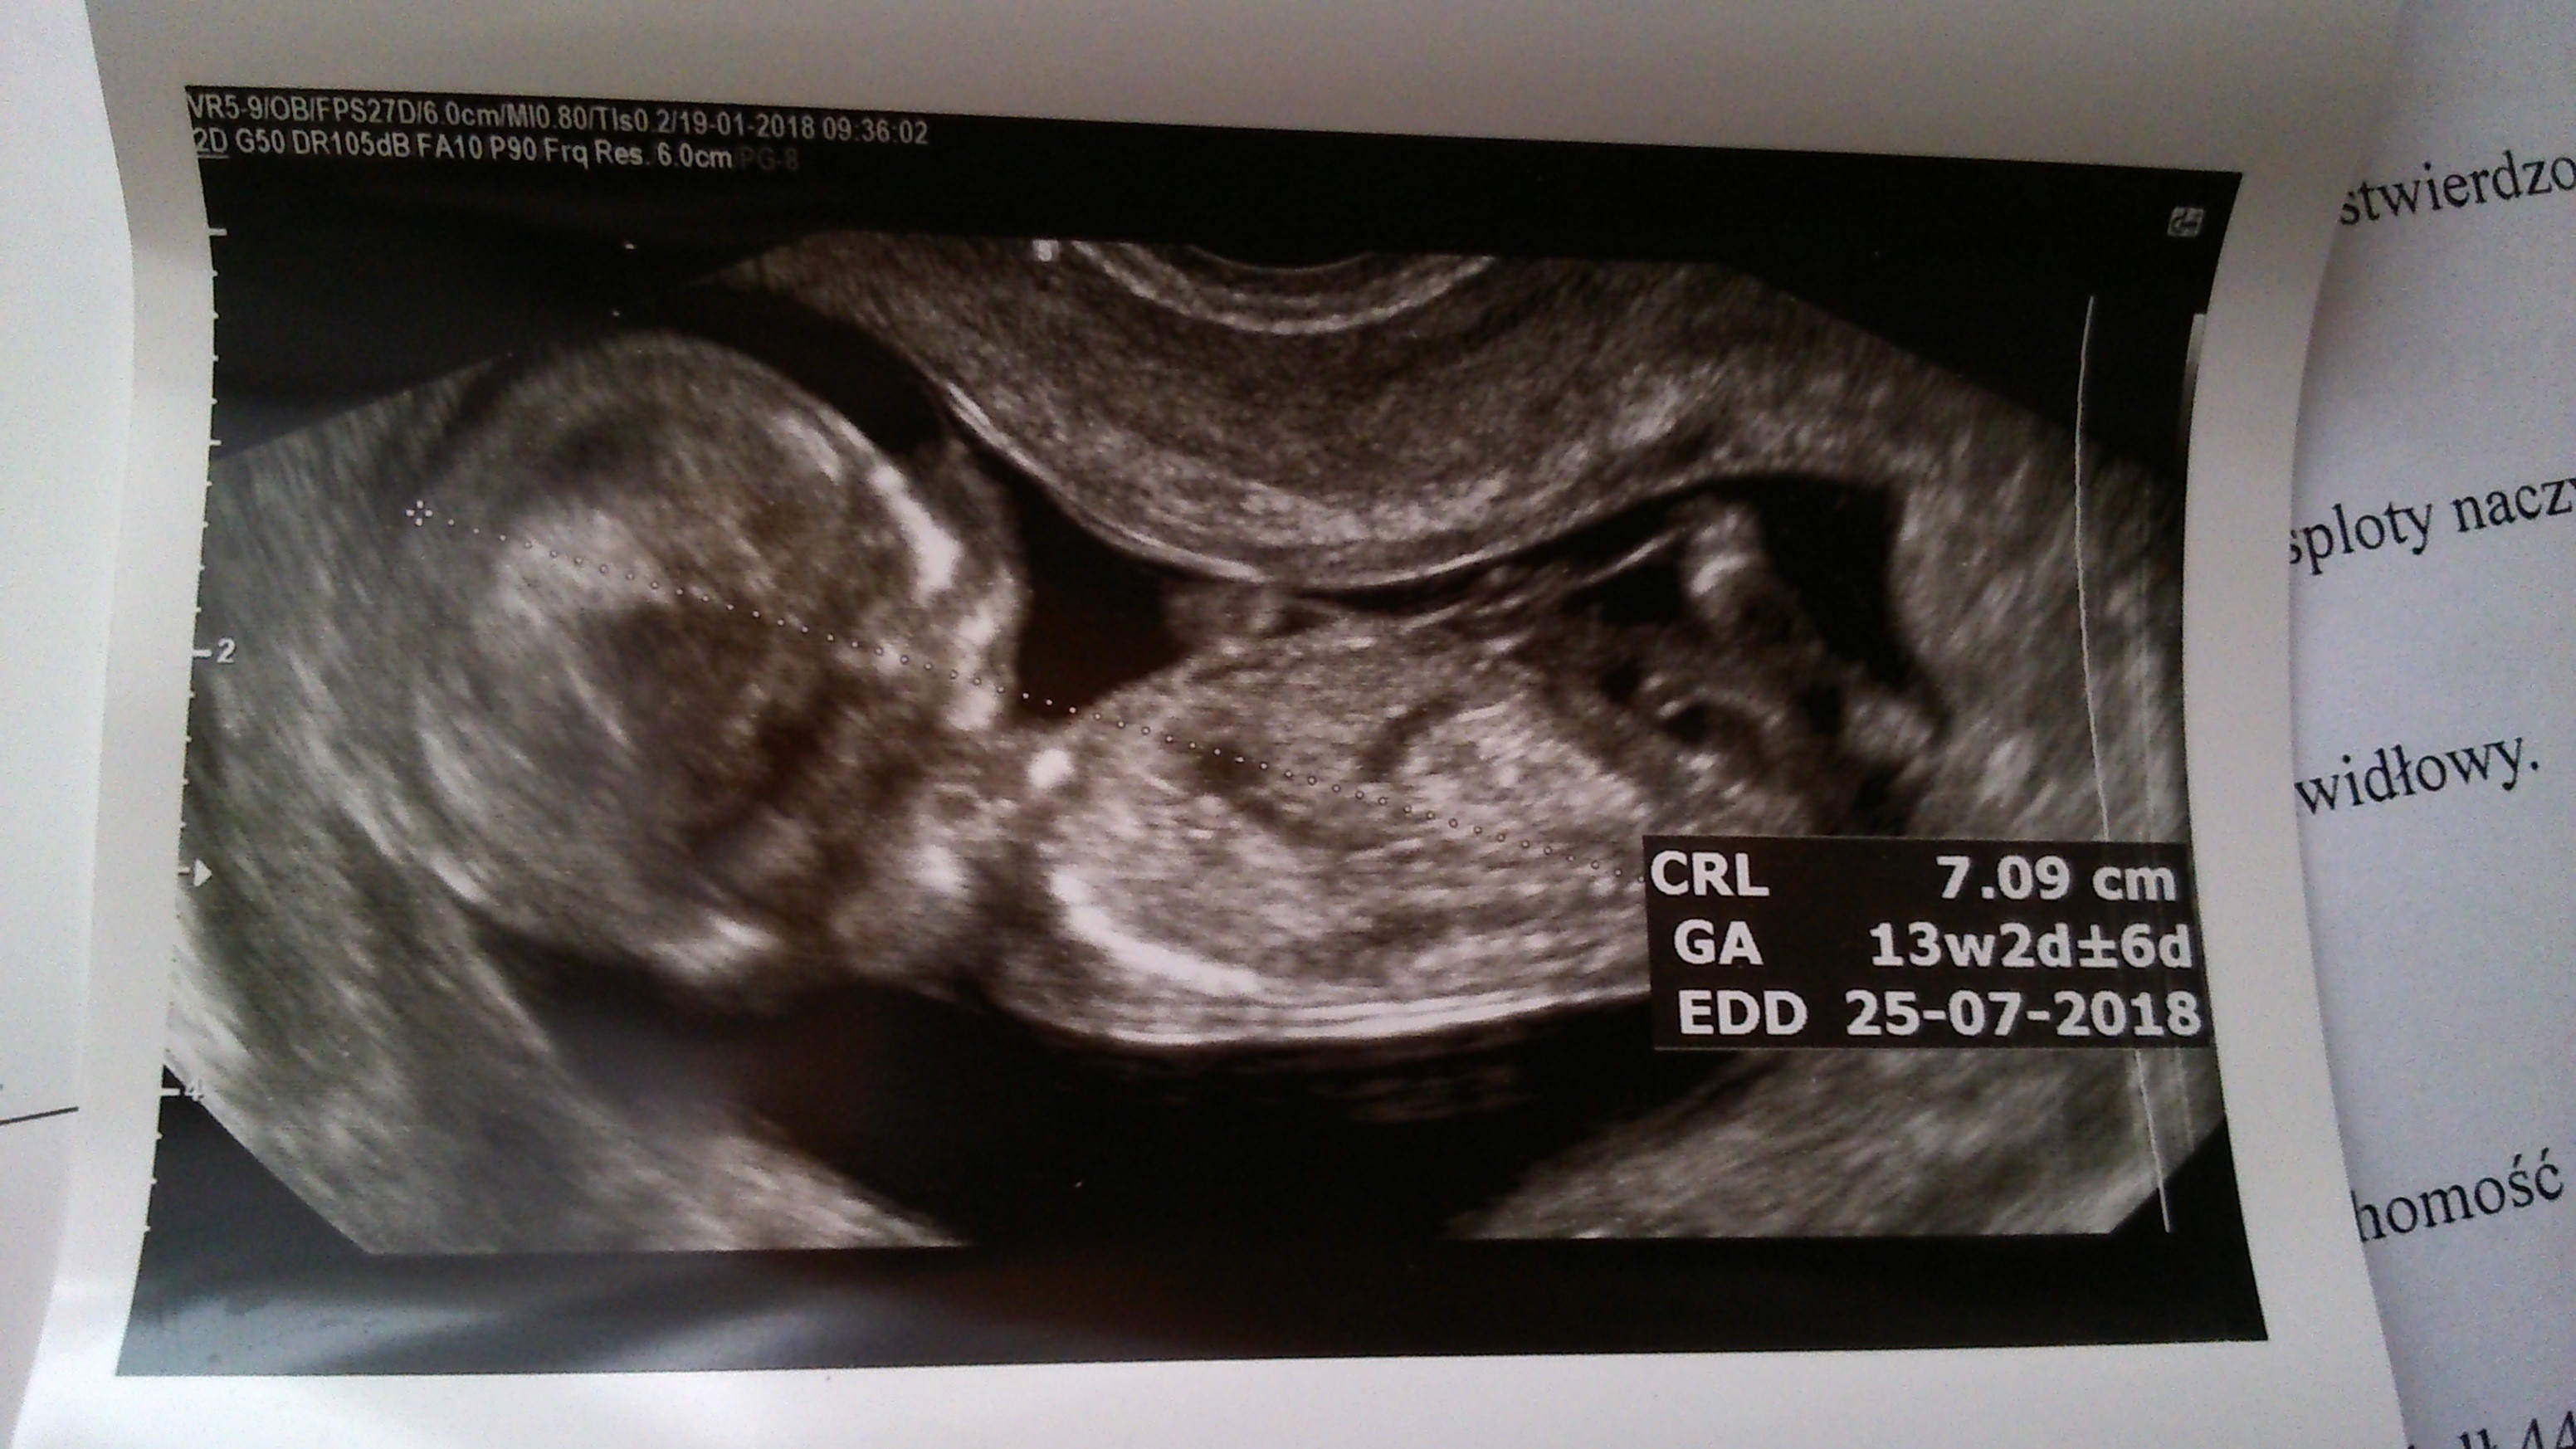

Zobacz załącznik 835955 Zobacz załącznik 835956 Zobacz załącznik 835953 Zobacz załącznik 835954 Ja jestem dopiero po usg prenatalnym, dzidzia ma 7 cm, według usg trochę starsza i termin przesunął się na 25.07. Dziecię w dobrym humorze uśmiechało się aż buzia otwarta była. Niestety nie chciało się pokazać. Na zdjęciu coś widać coś zwisa tylko nie wiem czy ty siusiak czy pepowia, zapomniałam zapytać.